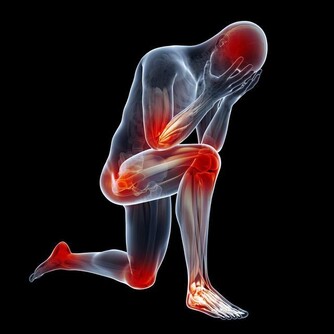

每到換季,總是疾病容易侵入身體的時候。在秋冬,是一個細菌高發的季節,人的身體在這個時間會變得比較脆弱,這就會給細菌進入身體創造了更多的機會。以下幾種疾病,就應當要引起注意。